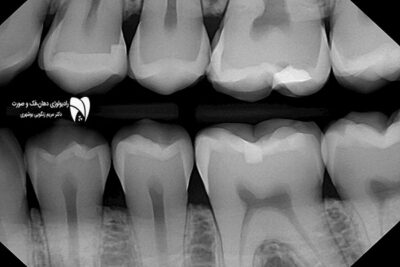

رادیوگرافی بایت‌ وینگ ابزاری کلیدی برای تشخیص پوسیدگی دندان است. در این مقاله با کاربردهای آن آشنا شوید. ضمنا به سوالات مهم در این مورد هم پاسخ دادیم.

رادیوگرافی بایت‌ وینگ: اهمیت و کاربرد آن در دندانپزشکی

رادیوگرافی بایت‌ وینگ موضوعی است که در این مطلب به بررسی آن به عنوان یکی از ابزارهای مهم د...

با رادیوگرافی بایت وینگ به تشخیص بیماری‌ های لثه بپردازید و از 3 مزیت مهم آن برای بررسی دقیق بیماری های لثه‌ها بهره‌مند شوید.

بررسی بیماری‌های لثه توسط رادیوگرافی بایت وینگ

تشخیص بیماری‌ های لثه توسط رادیوگرافی بایت وینگ موضوعی است که در این مطلب قرار است شما با ...